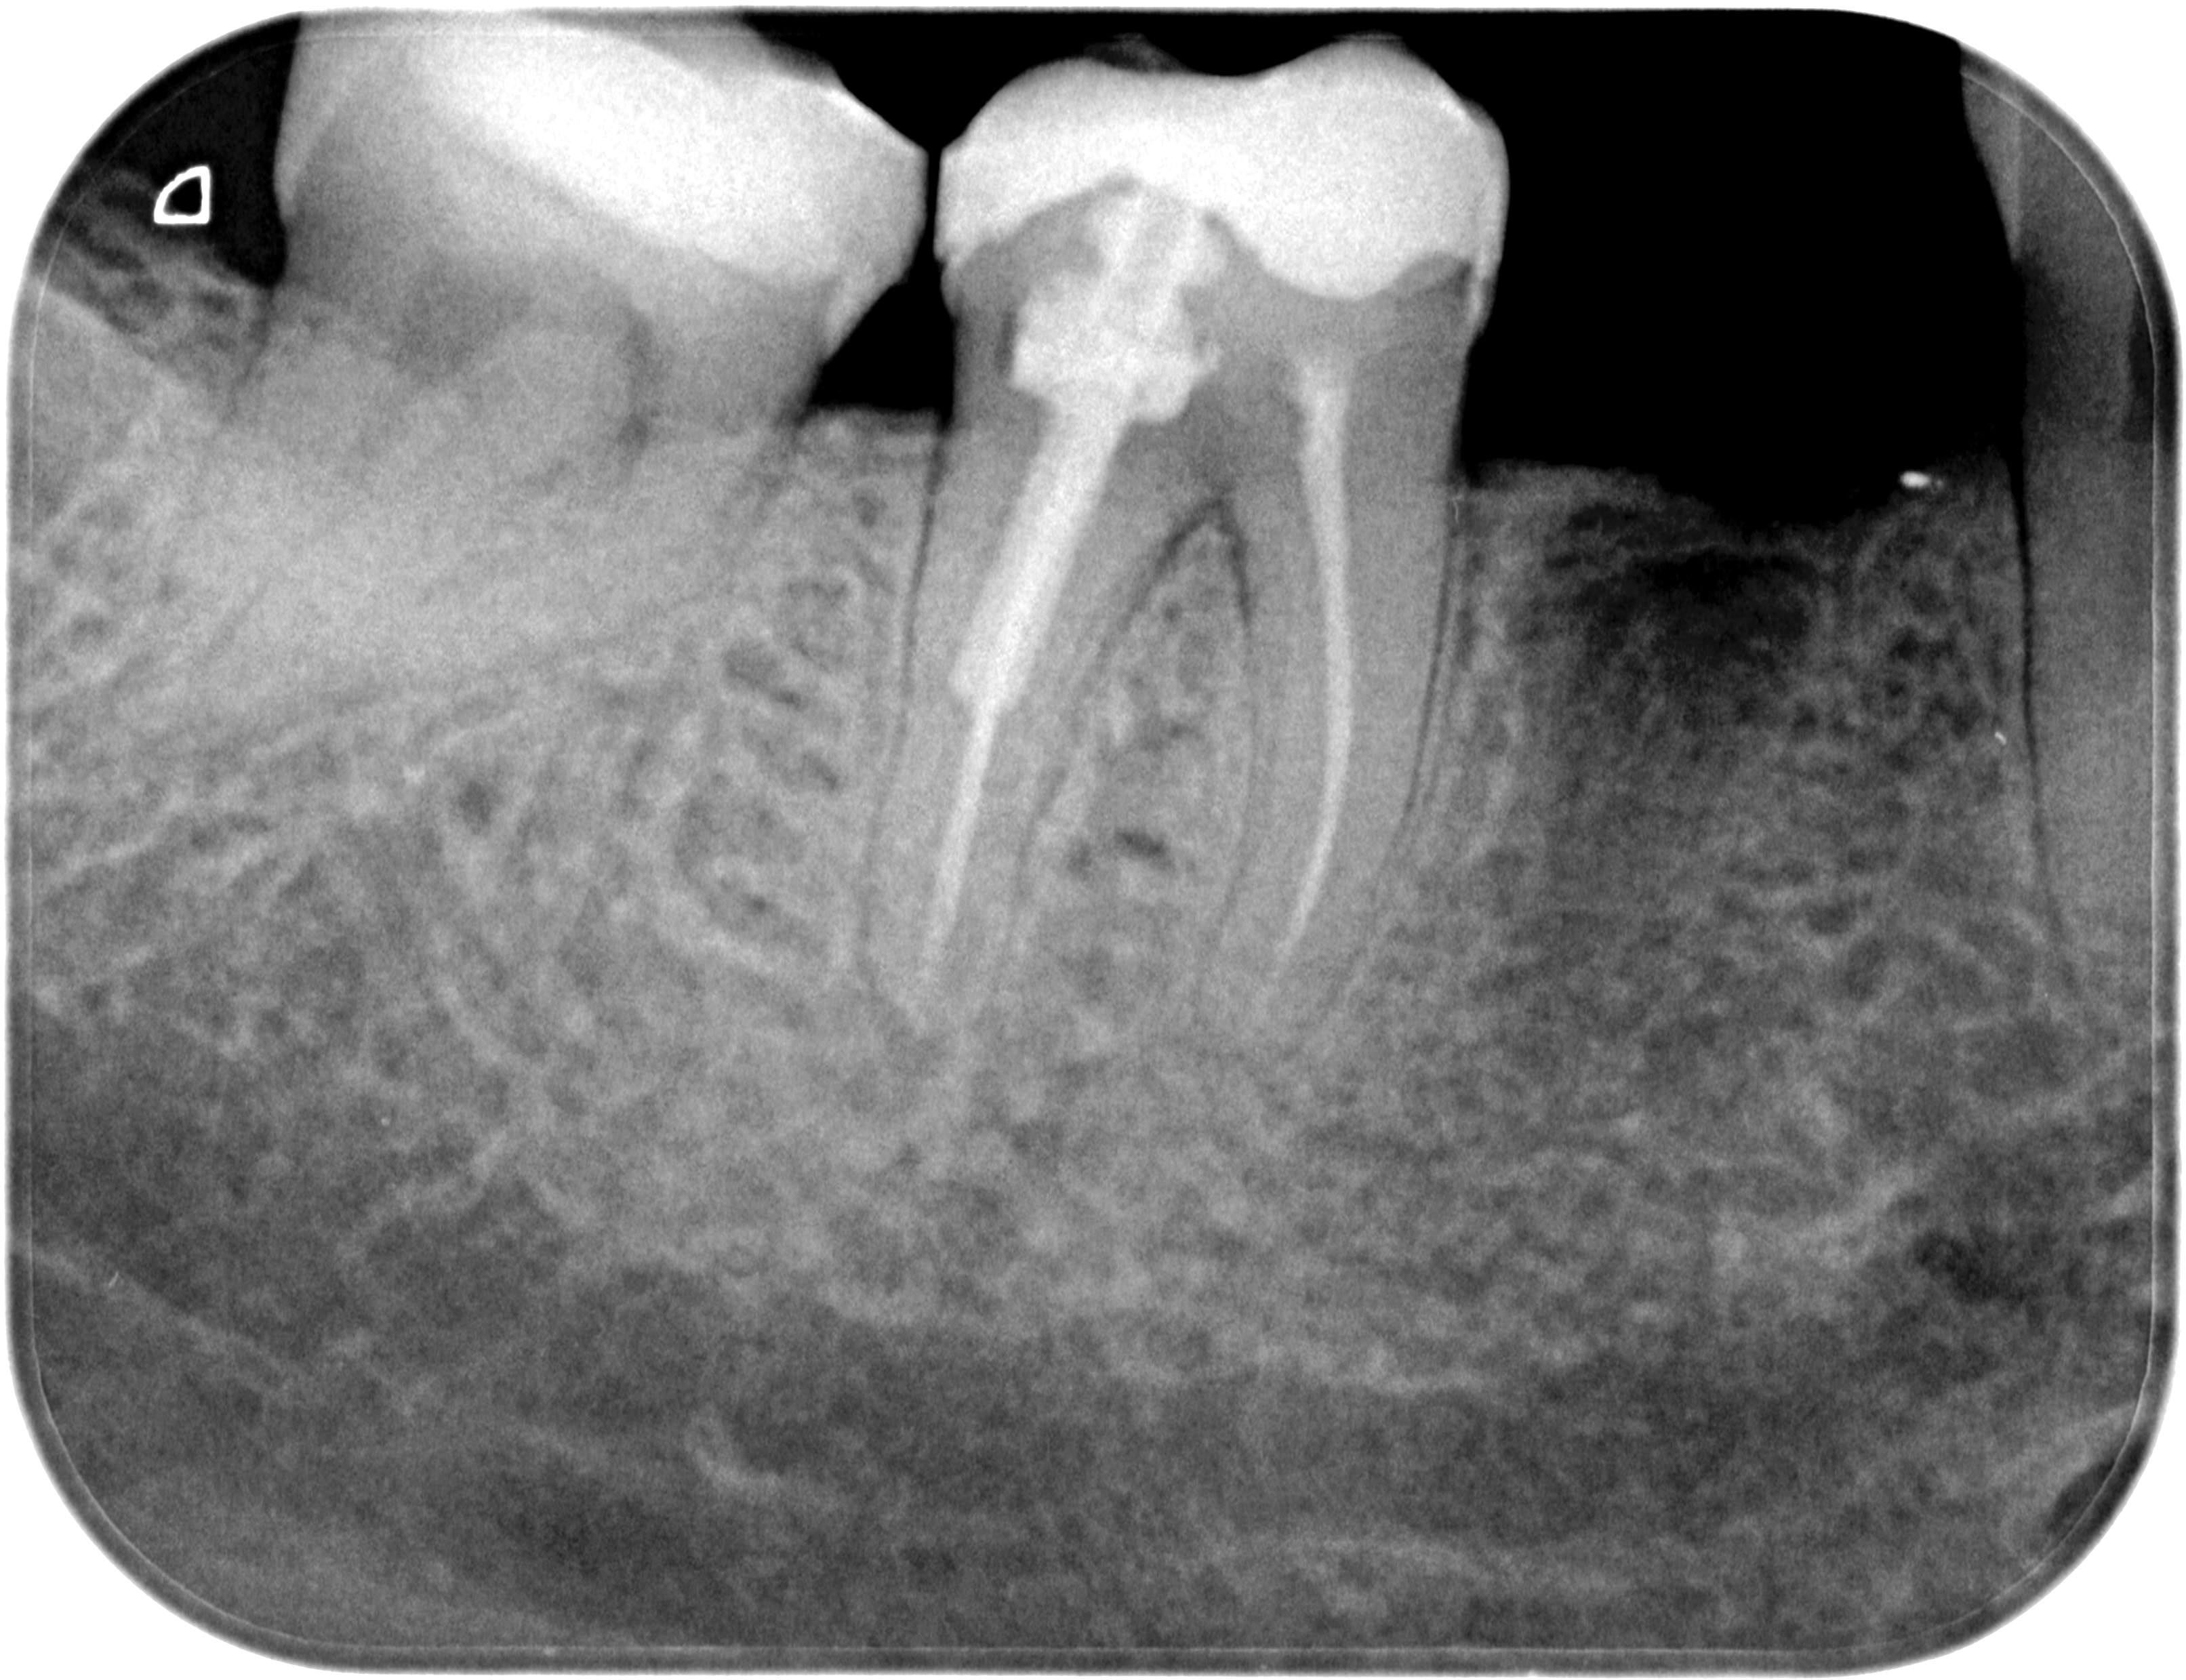

Resorption-1-5 Veröffentlicht 10. Juni 2013 am 3225 × 2479 in Was zeigt das DVT (4) ? Die Fälle Zahn 47, 46